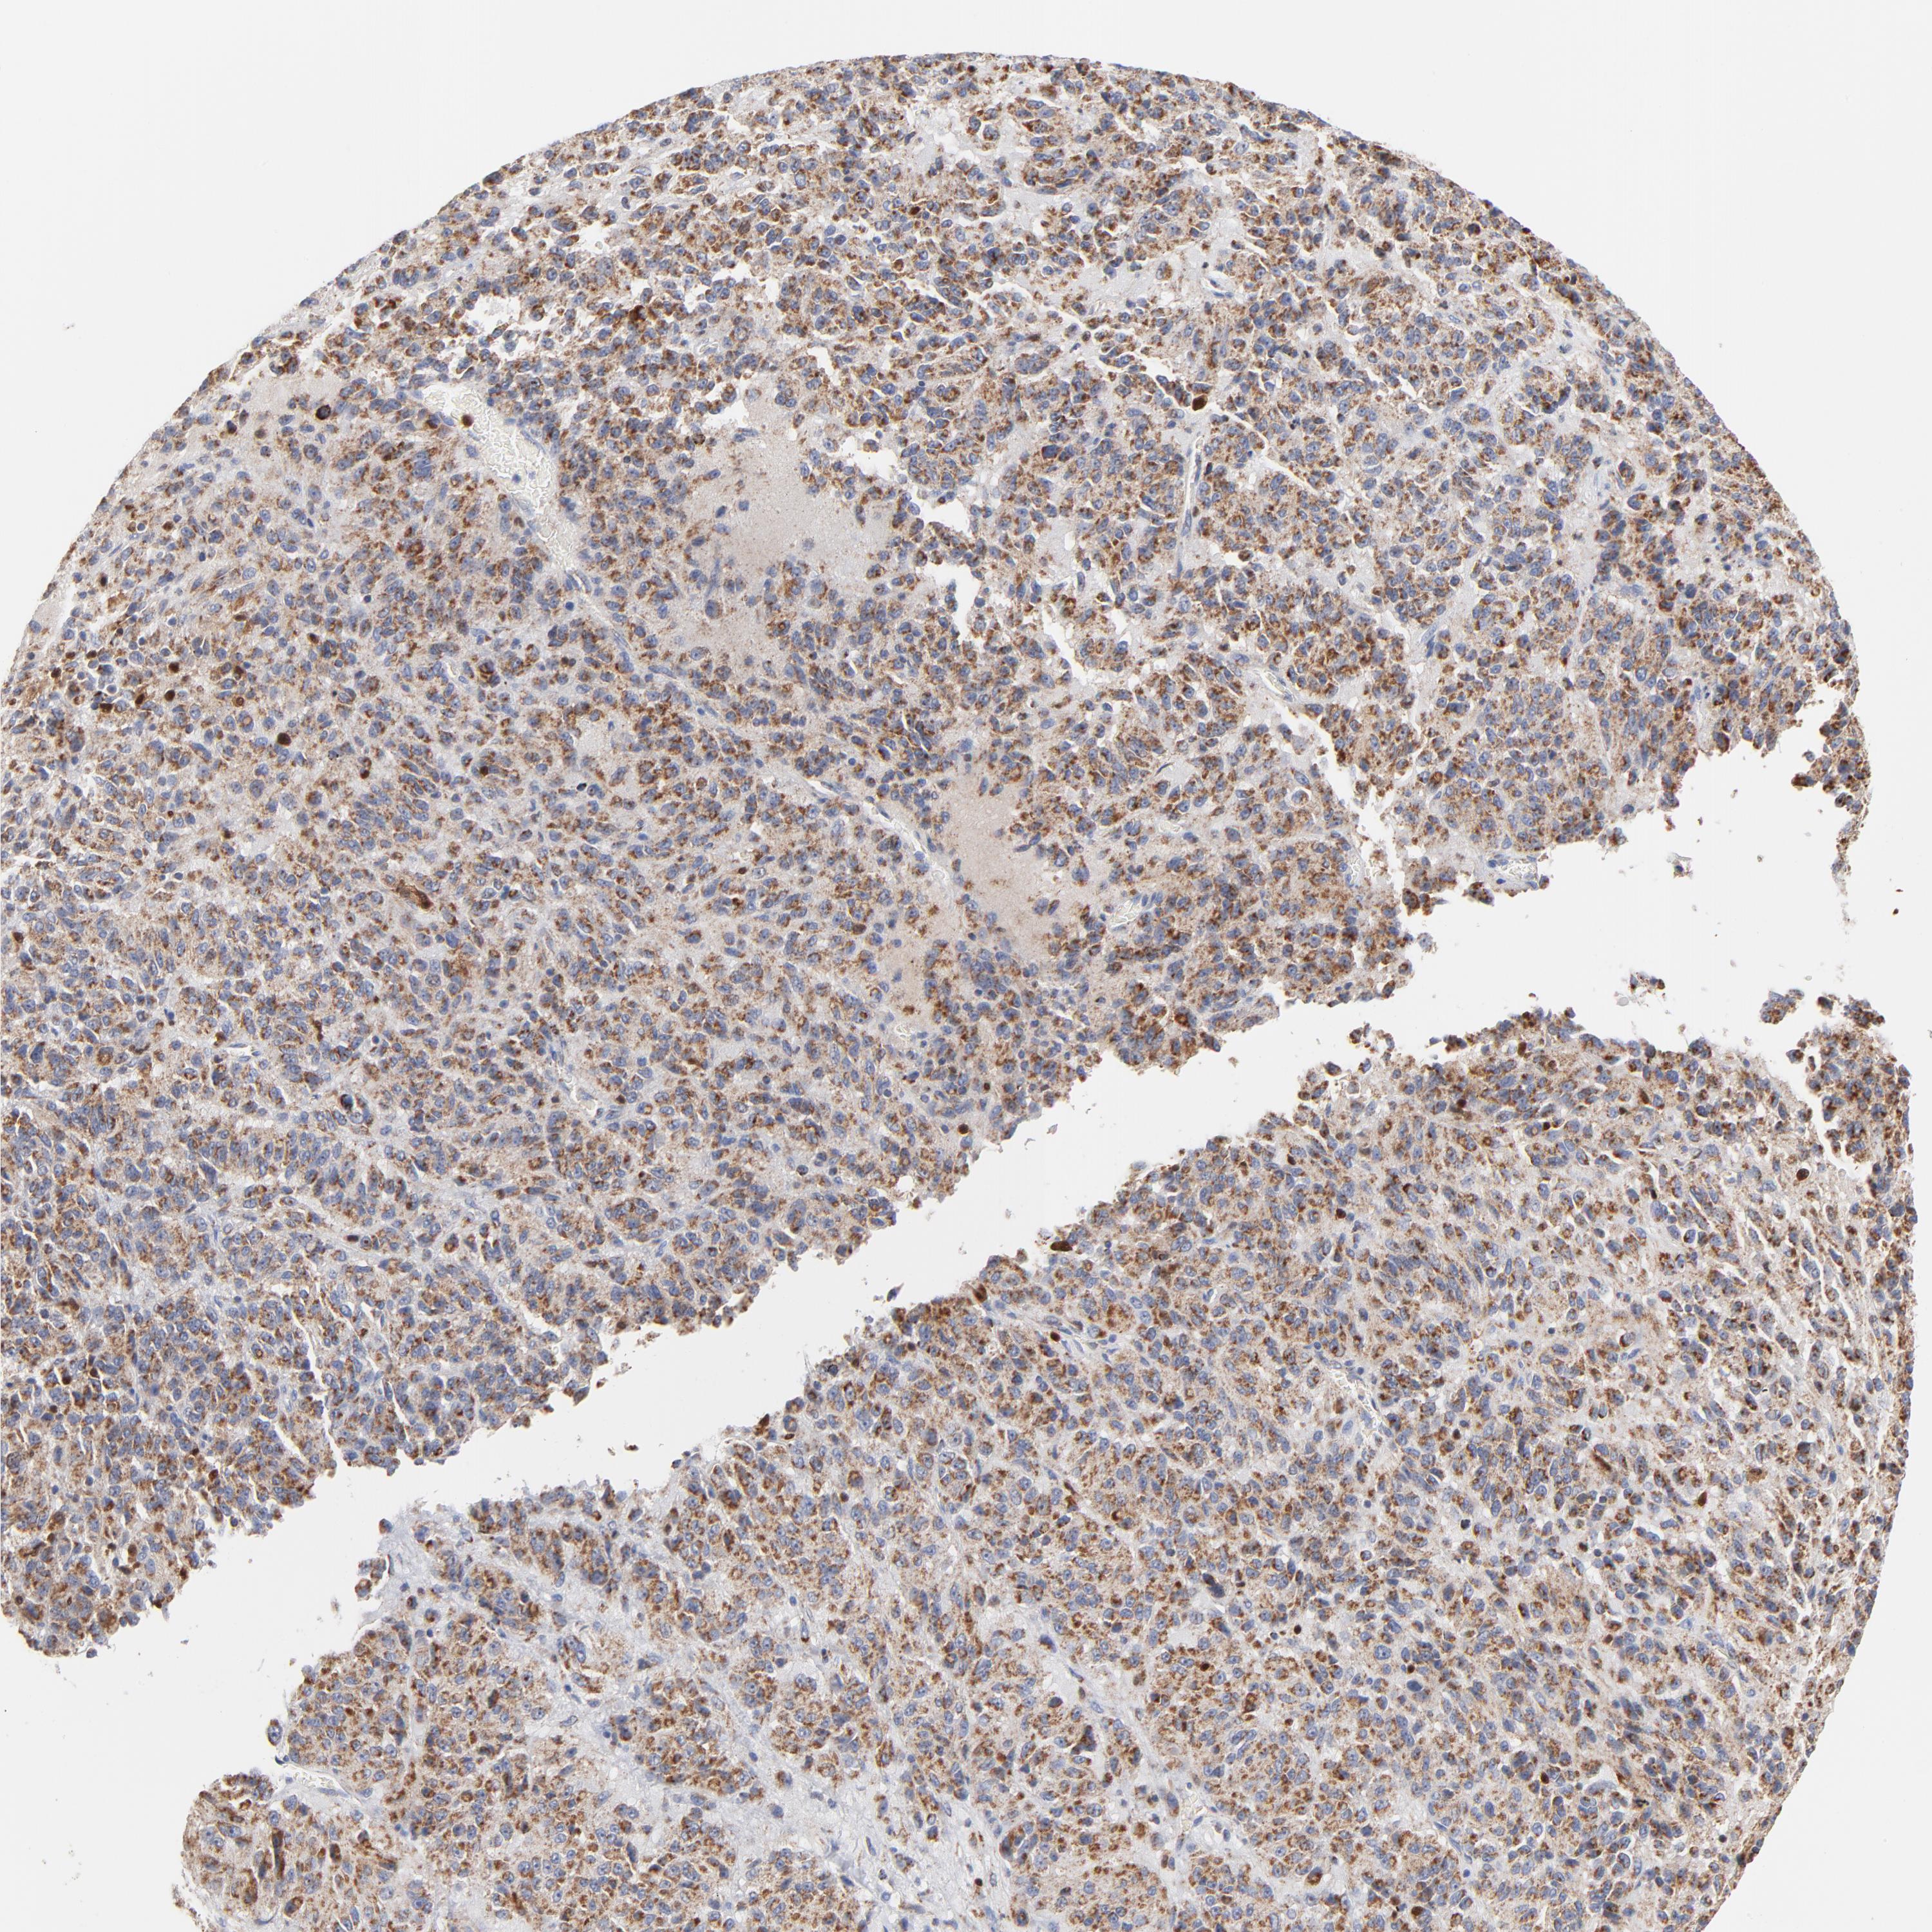

MELANOMA - Protein expressioni

A mouse-over function shows sample information and annotation data. Click on an image to view it in a full screen mode. Samples can be filtered based on level of antibody staining by selecting one or several of the following categories: high, medium, low and not detected. The assay and annotation is described here.

Note that samples used for immunohistochemistry by the Human Protein Atlas do not correspond to samples in the TCGA dataset.

Antibody stainingi

Antibody staining in the annotated cell types in the current human tissue is reported as not detected, low, medium, or high, based on conventional immunohistochemistry profiling in selected tissues. This score is based on the combination of the staining intensity and fraction of stained cells.

Each image is clickable and will lead to virtual microscopy that enables deeper exploration of all samples and also displays staining intensity scores, fraction scores and subcellular localization as well as patient and tissue information for each sample.

Antibody HPA001825

Antibody CAB003857

Staining

High

Medium

Low

Not detected

Intensity

Strong

Moderate

Weak

Negative

Quantity

>75%

75%-25%

<25%

None

Location

Nuclear

Cytoplasmic/membranous

Cytoplasmic/membranous,nuclear

Malignant melanoma, NOS

Malignant melanoma, Metastatic site